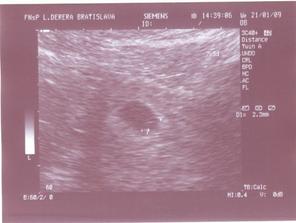

31.12.2008 som našla na teste vytúžené 2 //. Dúfam, že sa bábo bude mať v mojom brušku dobre. 21.1.2009 sa chystáme na prvé sono. Dnes sme boli na prvom sone a bábo je 2,3mm veľké (7tt+5d). Počula som tlkot srdiečka a rozplakala som sa. 🙂)